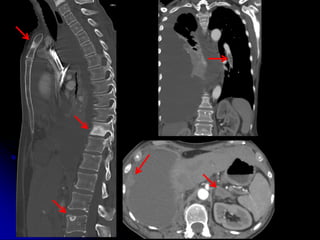

• CHEST/ABD/PELVIS/TSP/LSP

• IV contrast

• 1mm acquisition, displayed thicker

• Systemic arterial phase chest/upper abd

• Portal venous phase abd/pelvis

• Delayed phase upper abd

• Coronal, sagittal reformats

1 2 3 4

WHICH PATIENT HAS ACUTE FX WITH SUBSEQUENT FUSION?

3

T6 T6

L2